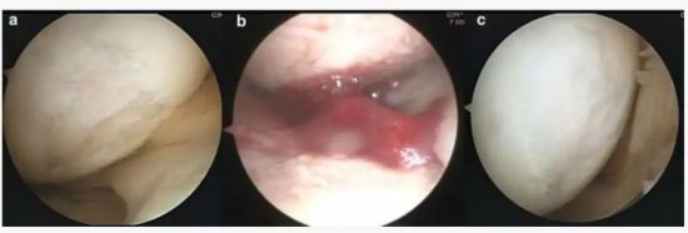

下图a为治疗前关节镜检查结果,,可以看出软骨存在缺损。。图b为脂肪间充质干细胞联合PRP治疗,,,图c为治疗后结果,,,,通过间充质干细胞治疗,,,,软骨得到了修复。。。。